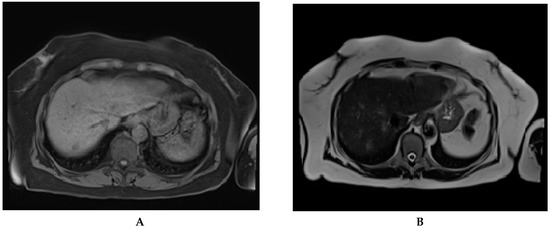

Some papers proved that non-contrast MRI was also sensitive in the detection of HCC nodules [,]. Performing a non-contrast MRI will reduce both examination time and costs []. Recent non-contrast-enhanced, abbreviated MRI protocols showed comparable results with contrast-enhanced CT and MRI in liver nodule detection (Figure 5) [].

Figure 5.

Abbreviated magnetic resonance imaging done for HCC surveillance in a 74 years old cirrhotic patient. A newly discovered nodule, in segment 7, is to be seen on the T1 vibe fs tra sequence (A) and T2 haste tra sequence (B). The nodule was later confirmed and classified as LI-RADS 5 by CEUS.